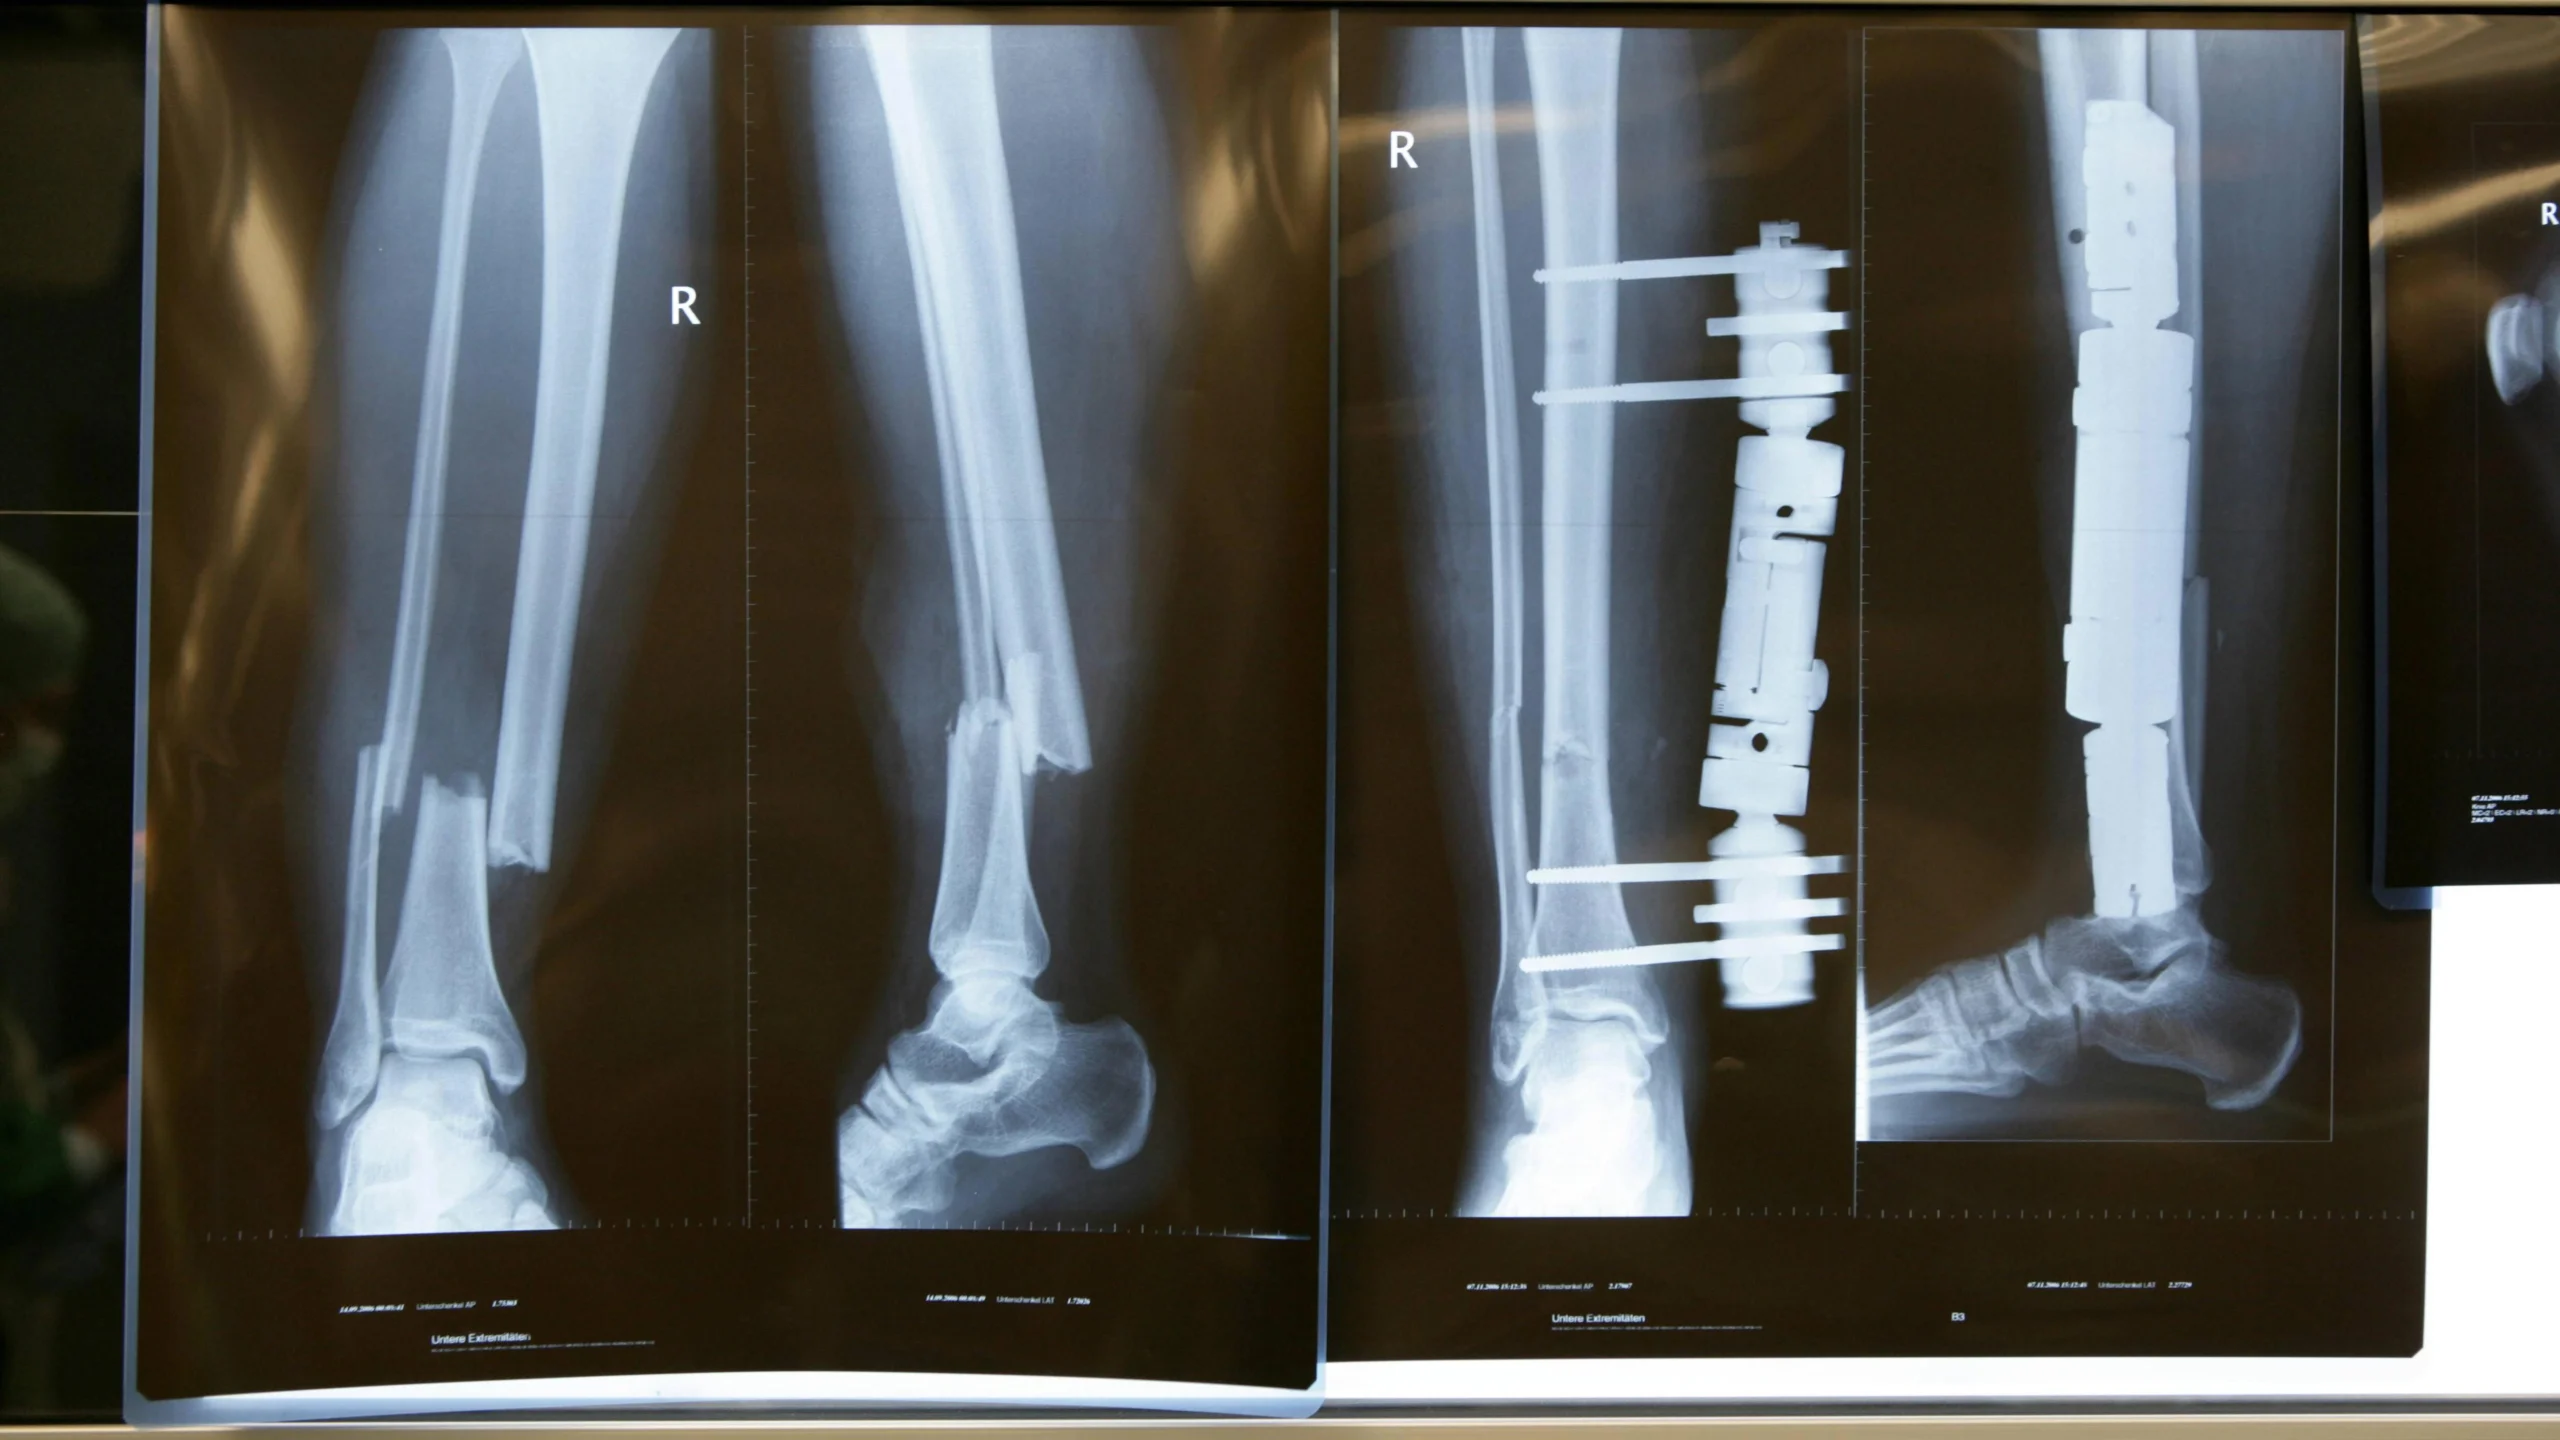

Diagnose eines Bruchs

Wenn Sie vermuten, dass Sie einen Bruch haben, ist es wichtig, sofort einen Arzt aufzusuchen. Der Arzt wird Ihre Krankengeschichte erfragen, eine körperliche Untersuchung durchführen und möglicherweise bildgebende Verfahren anordnen, um die Diagnose zu bestätigen.

Die folgenden bildgebenden Verfahren werden häufig verwendet, um Brüche zu diagnostizieren:

- Röntgenaufnahme: Röntgenaufnahmen sind die am häufigsten verwendeten bildgebenden Verfahren zur Diagnose von Brüchen. Sie zeigen die Knochenstruktur und können einen Bruch klar sichtbar machen.

- Operation: In einigen Fällen kann eine Operation notwendig sein, um einen Bruch zu behandeln. Dies kann notwendig sein, wenn der Bruch schwerwiegend ist, wenn der Knochen nicht richtig verheilt oder wenn die Knochenstücke versetzt werden müssen.